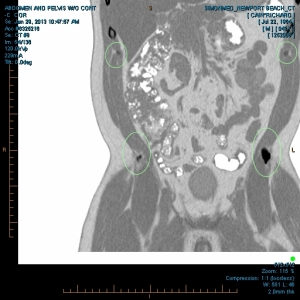

“My family and I have been the subjects of Government funded human research and/or hate crimes. These crimes are being covered-up by using the words National Security. The fact that my two minor children have the same and/or similar devices in their little bodies speaks for themselves. My sons were ages 3 and 4 when the discoveries took place. Their x-rays, blood & urine analysis present the true facts. The devices can only be introduced into the body, while being in a medical facility. All three of us were patient of the same defendant hospital.

“The CD-ROM from CCAI depicts the same images that are attached. I will bring the 01/03/2012 Simonmed Imaging CT scan which also depict foreign objets in the heart and chest.”

“Please take a look at both X-rays. Superimpose the foreign objects AKA EKG clamps and you will find that they are the same devices. when have you ever seen an EKG clamp place sideways in the abdomen? Both x-rays have been confirmed by Radiologist Louis Teresi as having foreign body reactions in the abdomen, right and left flanks.

“The obvious implant in the 2012 x-ray stands out from the others, because it at the time had not embedded into my flesh (heart).”